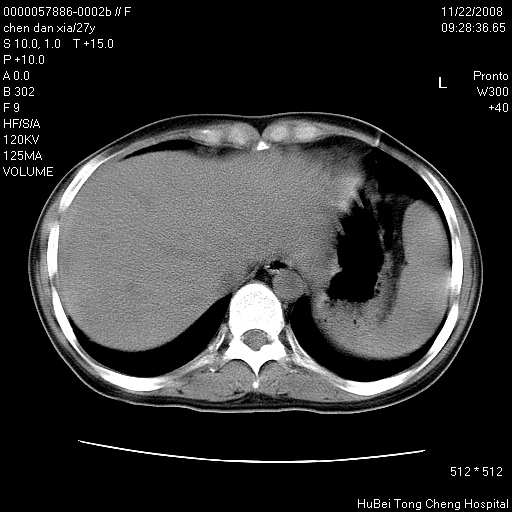

标题: CT16752:F,27Y。发热咳嗽20余天,伴盗汗。 [打印本页]

标题: CT16752:F,27Y。发热咳嗽20余天,伴盗汗。

右下肺见片絮状影,两肺野内分布不均的小结节影,结核并肺内播散可能性大,建议结合实验室检查 .

右下肺纹理模糊;纵隔可见肿大淋巴节;右心缘旁结节,边缘光滑,纵隔窗病变范围较肺窗明显小,首先考虑右下肺结核,不排外淋巴瘤

双肺纹影普多,部分呈网状,支炎或淋巴管炎?

纵隔内淋结肿

局部胸膜增厚

下肺结节,结节内钙化,肺门纵隔淋巴肿大 结核可能性大

1)考虑两肺感染性病变。2)纵隔淋巴结肿大。